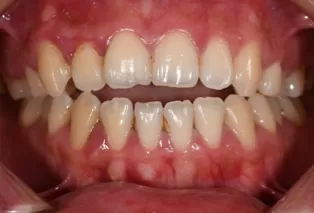

Photos intra-orales après traitement